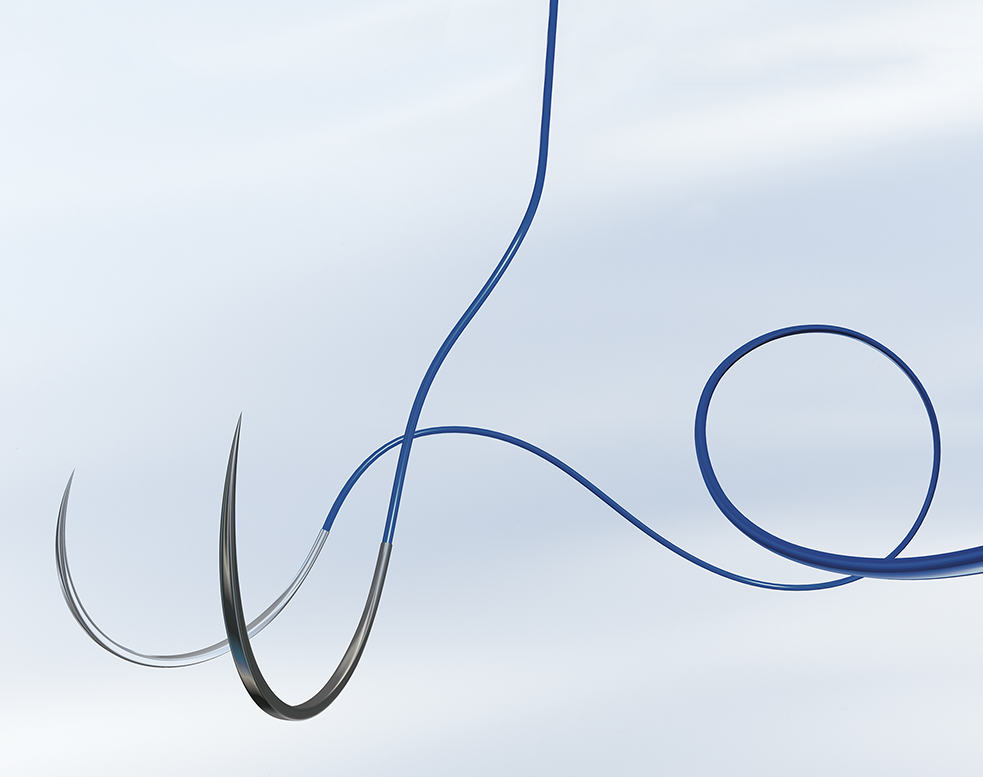

Назва профілю: Нитка хірургічна стерильна з голкою, Поліпропілен і поліетилен, Монофіламентна, 3/0(2,0), довжина нитки, 0,9, м, не розсмоктується, без покриття, 1/2 кола, довжина голки, 22, мм, Колюча, Двох-голкова, без петлі, без насічки, Синій

Тип згину голки

1/2 кола

Кількість голок

Двох-голкова

Довжина голки, міліметр

22

Тип голки

Колюча

OPTILENE, розмір USP 3/0 (2) довжина 90см 2 колючі голки 1/2 кола, довжина (мм) 22 серцево-судинна, пакування RCP

OPTILENE, розмір USP 3/0 (2) довжина 90см 2 колючі голки з коротким ріжучим вістрям, 1/2 кола, довжина (мм) 22 серцево-судинна, пакування RCP

OPTILENE, розмір USP 3/0 (2) довжина 90см 2 колючі голки з коротким ріжучим вістрям, 1/2 кола, довжина (мм) 22 серцево-судинна, пакування RCP

OPTILENE, USP 3/0 (2) довжина 90см 2 колючі голки 1/2 кола, серцево-судинна

OPTILENE, розмір USP 3/0 (2) довжина 90см 2 колючі голки 1/2 кола, довжина (мм) 22 серцево-судинна, пакування RCP